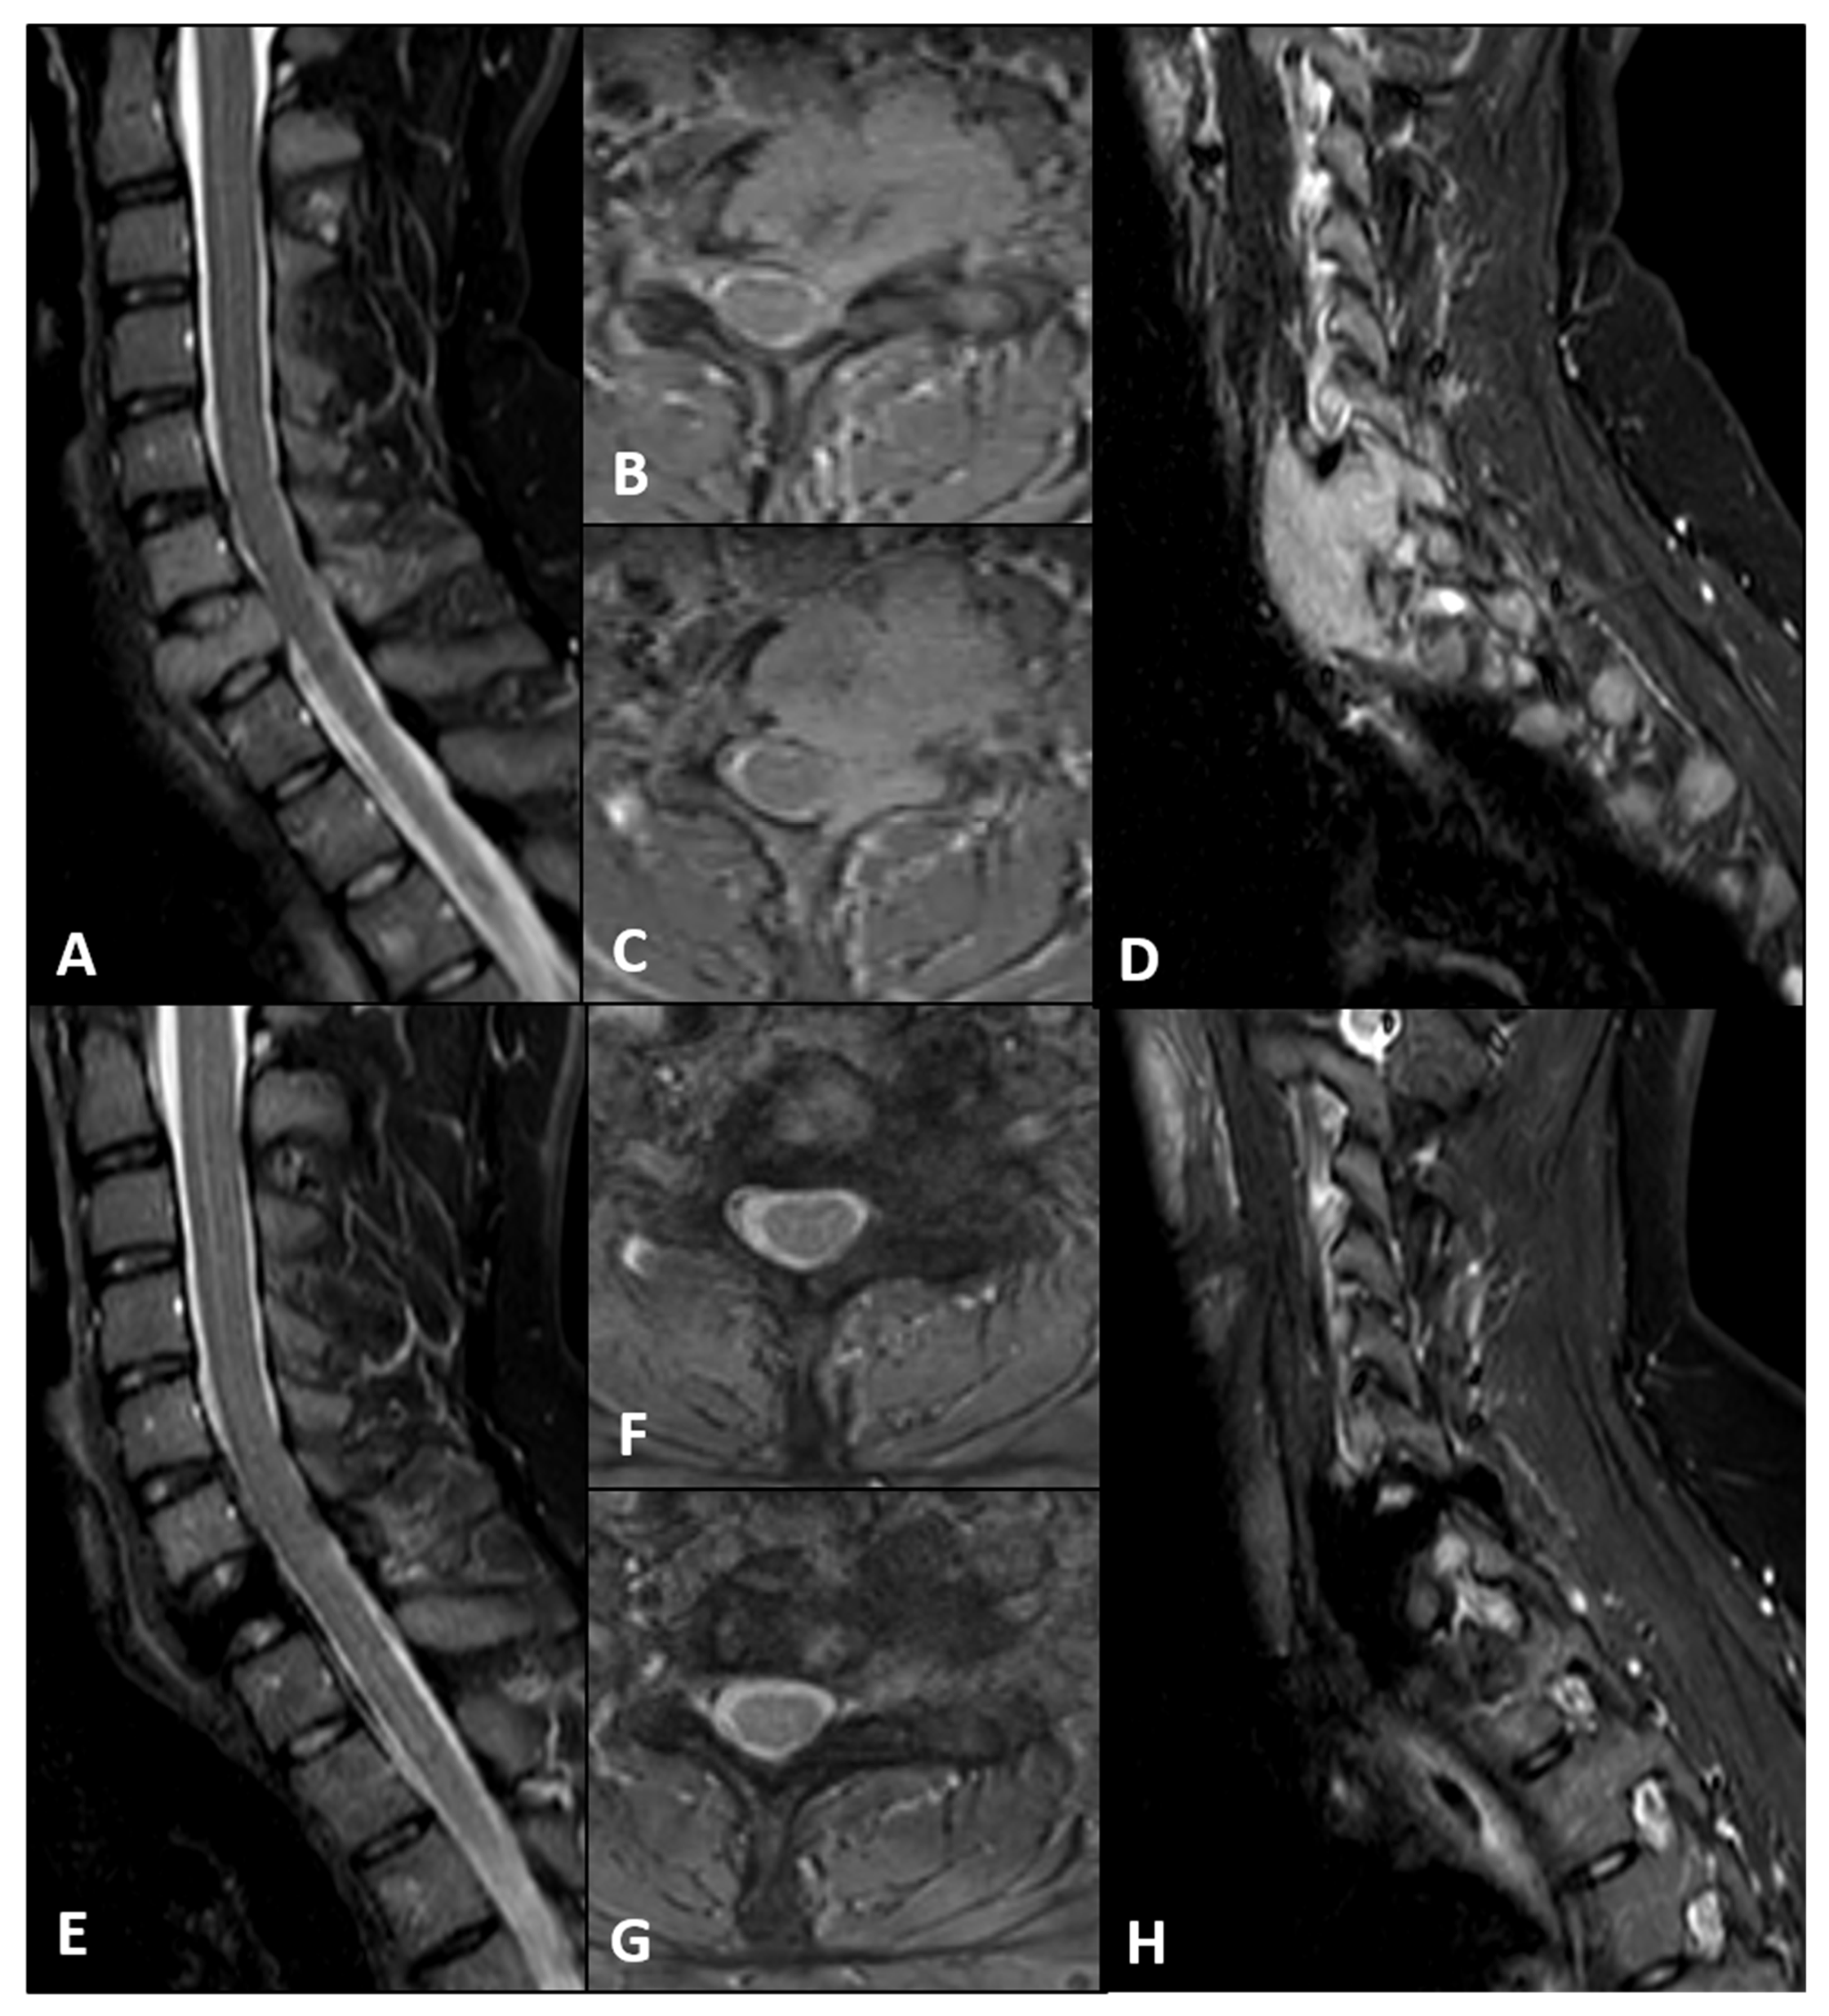

2. Case Presentation

4. Discussion

4.1. CFR-PEEK Instrumentation: Potential Advantages

4.2. Robotic Planning Under Hardware Constraints: Approach, Safety, and Alternatives

4.3. Multimodal and Complication Management